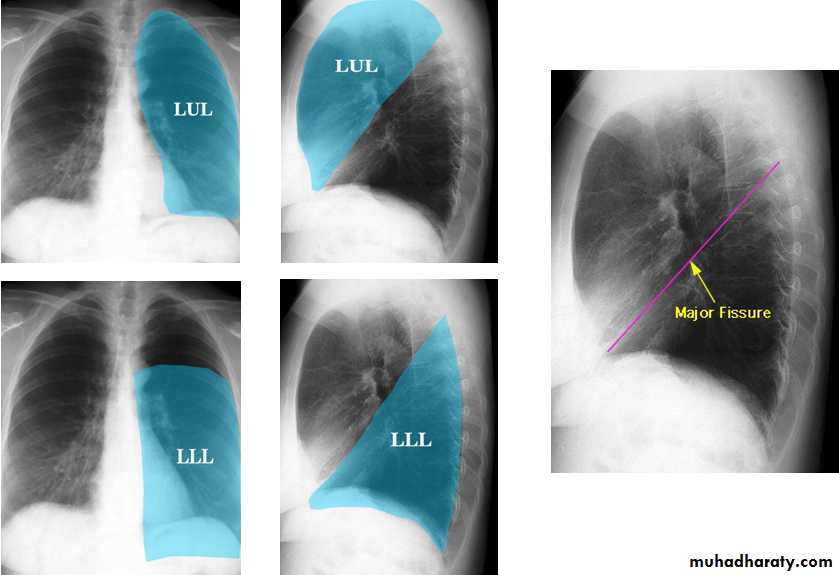

Radiologic anatomy of the RT lung lobes

Radiologic anatomy of the LT lung lobes

Lobes and fissures

This cut-out of a lateral chest x-ray shows the positions of the lobes of the right lung

On the left the oblique fissure is in a similar position but there is usually no horizontal fissure, and so there are only two lobes on the left.

The horizontal fissure (right) is often seen on a normal frontal view

The oblique fissures are often seen on a normal lateral view .